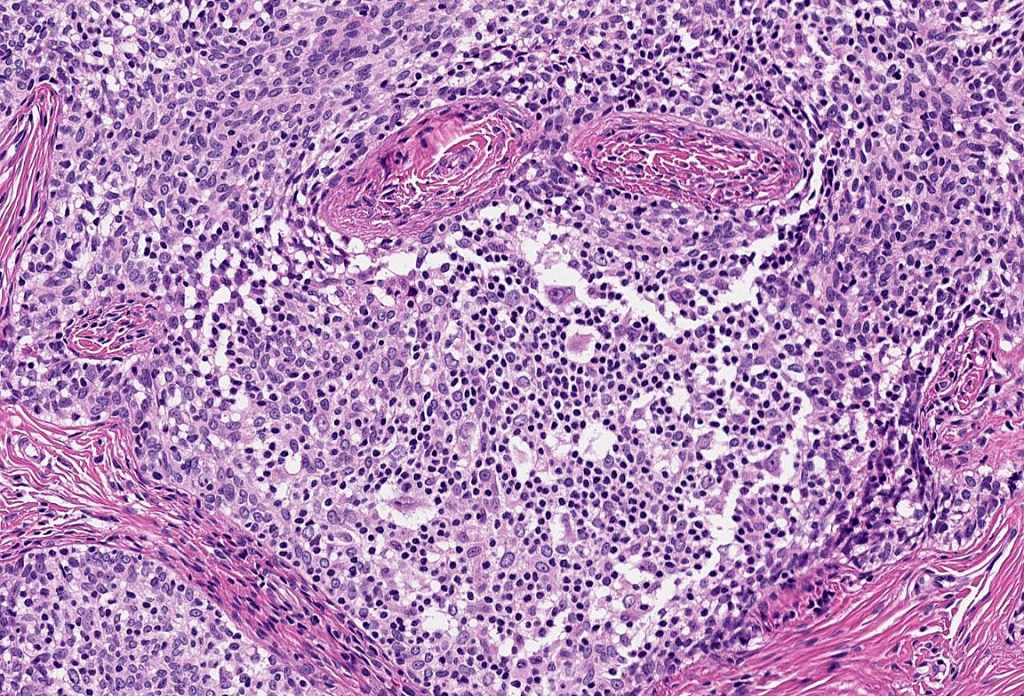

Histological features

•Irregular lobules of epithelial cells embedded in a dense fibrous stroma

•Peripheral rim of darkly staining basaloid cells surrounding larger pale staining cells with vesicular nuclei with often prominent eosinophilic nucleoli

•Admixed lymphocytes (an obligatory feature)

•Germinal centers sometimes present

•T-cells>> B-cells (CD4>CD8)

•+/- Occasional CD30 +ve cells (Reed-Sternberg-like cells)

•+/- CK20 +ve Merkel cells

•S100, CD1a +ve Langerhans cells, CD68 +ve histiocytes